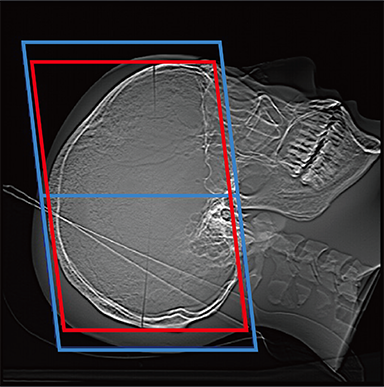

FCT iStream automatically*2 sets the scanning range using the scanogram image by AutoPose function. Since the margins can be set in advance, the range can be customized according to the preference of the facility. iTilt automatically creates and enables observation of tilted images during scanning.

When set to OM Line

When set to SM Line

When set to RB Line

Red: automatically set position, Blue: automatically set position + margin setting position